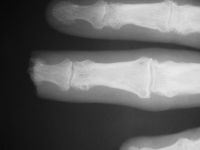

| Case

4. A dog bit off this young man's index fingertip. Although the PA Xray looks as though the bone was kept, additional views show an amputation through the tuft. |